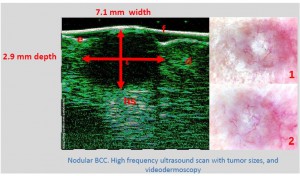

-Γενικά πεδία εφαρμογής ογκολογίας

-Απλά διαγνωστικά κριτήρια κακοήθειας όγκου δέρματος

-Μελάνωμα

-Μέτρηση επιπέδων Breslow και Klark σε έμβιο οργανισμό (IN VIVO)

-Διαφοροποίηση τύπων βασικοκυτταρικού καρκινώματος